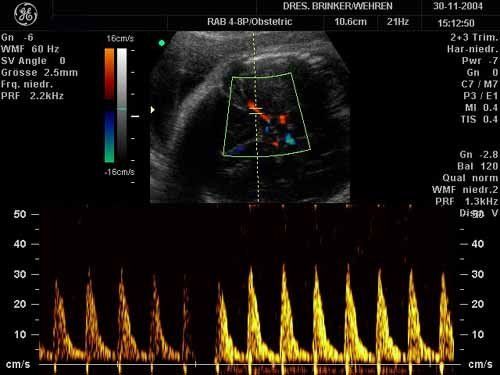

Farbcodierte Doppler-Ultraschallunterschung

Darstellung der Blutversorgung des kindlichen Gehirns